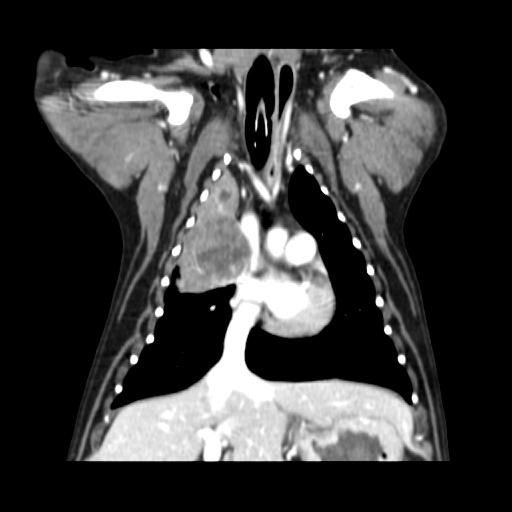

엑스레이 사진과 CT 사진(흉부 앞, 우측 옆)은 첨부하였습니다.

폐 우측 위쪽에 원발성 암이 발생한 것으로 보였습니다.

식도와 심장을 눌러서 기침을 발생시켰습니다.

나쁜 소식은 심장과 혈관이 위치한 안 좋은 부위에 암이 있다는 것이고,

좋은 소식은 심장과 혈관과 아직 붙지 않고 떨어져 있다는 것이었습니다.